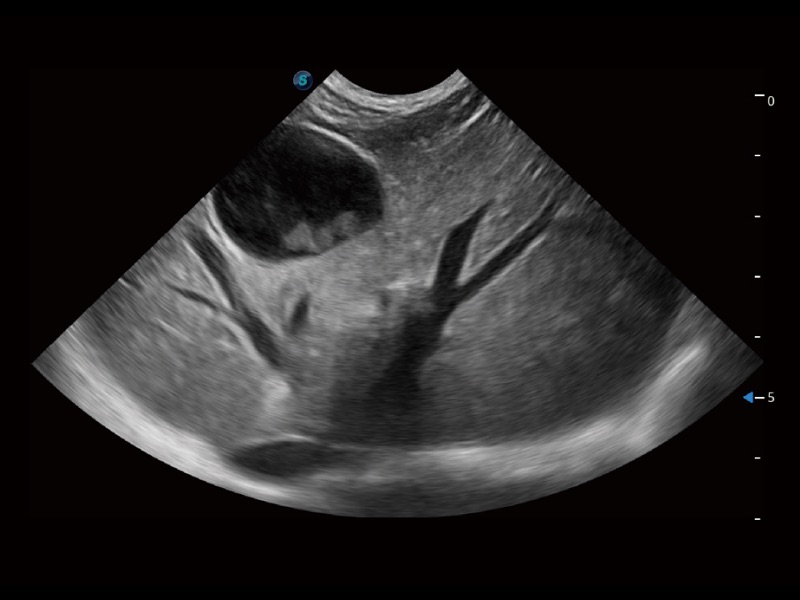

大型犬、马科、农场动物及大型异宠动物

通过创新的 Matrix E自适应滤波器和超长时间域算法,极大提升超低速微细血流的检出能力,同时更精准地滤除软组织和噪声信号,为兽用医生提供以往无法通过常规血流获得的疾病诊断信息。

通过色彩血流和实时宽景相结合,可观察到完整的静脉或动脉的血流,方便医生检查。实时扫查过程中,如有任何操作失误也可以很容易地进行回扫擦除,而不会中断扫查。

ProPet 70专为动物医生设计,对不同的动物体型和生理结构作出了针对性的优化。通过动物影像专用软件,可满足个性化的应用需求,帮助动物医生获得更精确的诊断数据。